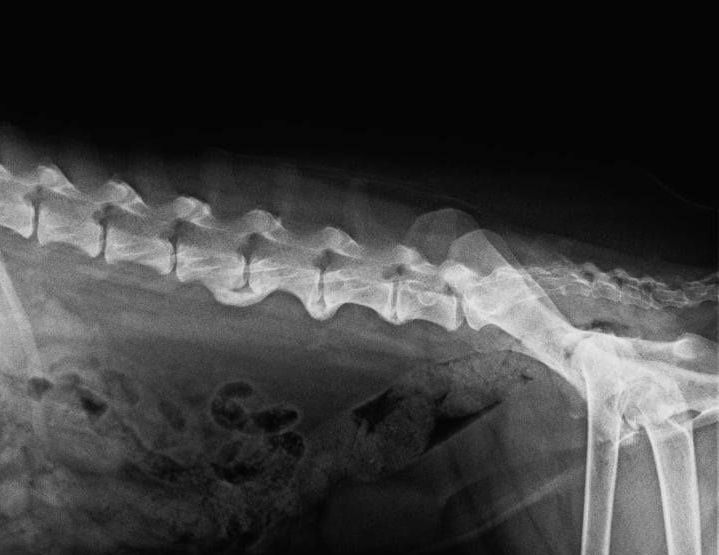

Hunde mit Erkrankungen des Bewegungsapparats profitieren häufig besonders von der Anwendung der Massagen, denn durch die mit ihrer Erkrankung einhergehenden Schonhaltung, kommt es sehr häufig zu Verspannungen im Bereich des Rückens oder der Gelenke. Die Gelenke können nicht mehr endgradig bewegt werden, was widerrum neue Schonhaltungen nach sich zieht. Erst wenn diese Verspannungen aufgelöst sind, macht eine weitere Behandlung z.B. in Richtung Muskelaufbau Sinn, denn erst dann wird der Hund nicht mehr in eine Schonhaltung fallen.